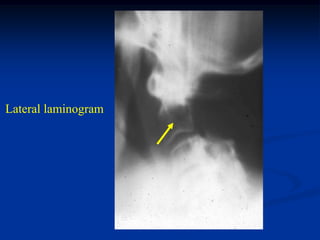

Case #1141

83 year male with lytic

prostate metastasis to

C-2

Lateral laminogram

Photomic